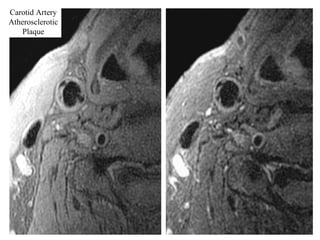

The document describes the Pathway MRITM Carotid Array coil, which is designed for high resolution imaging of small soft tissue structures like the carotid arteries. It provides images showing atherosclerotic plaque buildup in the carotid arteries, including plaque in the common carotid artery, carotid bifurcation, and internal carotid artery stenosis and plaque.